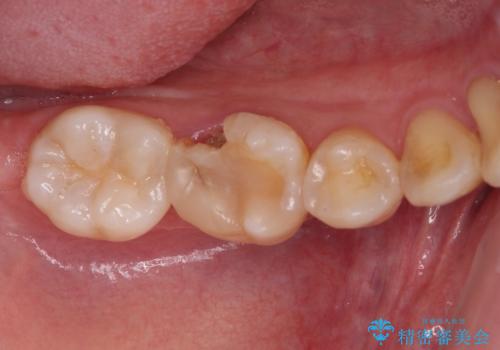

- 奥歯が食事中に歯が欠けて、しみて痛いとのことで来院された患者様です。

レントゲン写真からも、舌側に大きな虫歯があることが分かりました。

症状から神経を取り除く可能性も考慮し、オールセラミッククラウンにて補綴治療することとしました。